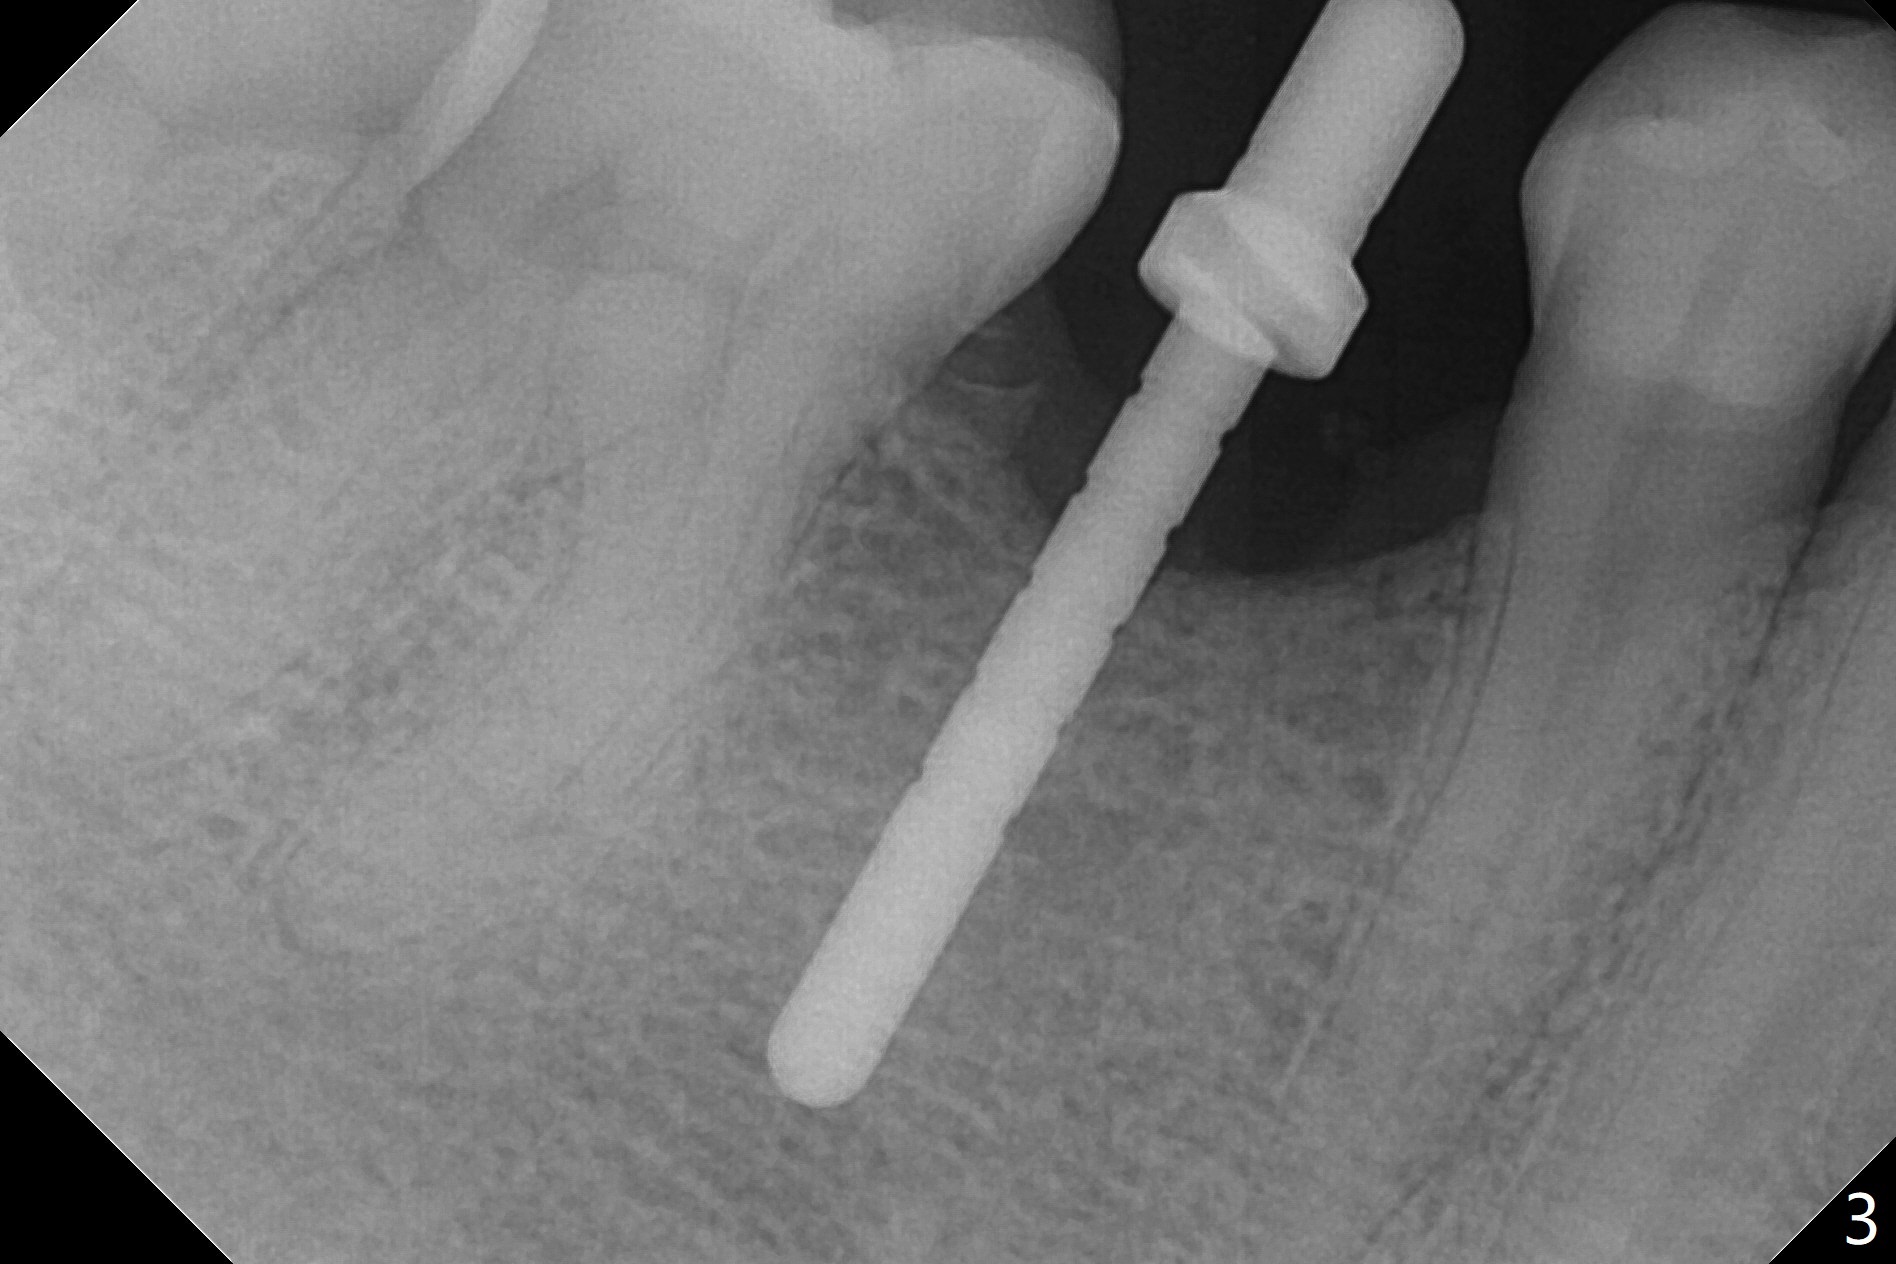

The base of the edentulous ridge at #29 looks wide (Fig.1), but the most coronal portion is the thin soft tissue (Fig.2).  It appears that there has been bone resorption since extraction.  The initial osteotomy depth is 11.5 mm (Fig.3).  Since the Mental Loop seems to be nearby, the depth of subsequent osteotomy (3 mm) remains the same (Fig.4).  Although the final depth of osteotomy is 13 mm, the implant placed is short (3.8x11.5 mm, Fig.5,6), as compared to the immediate implant (3.8x18 mm) at the contralateral side (#20).  There is mild bone resorption mesially 4 months postop (Fig.7).  The crown is loose (poor osteotomy position, guide necessity) 7 months post cementation immediately prior to 18 cementation, although there is no gross bone losss 1 year 7 months post cementation (Fig.8).